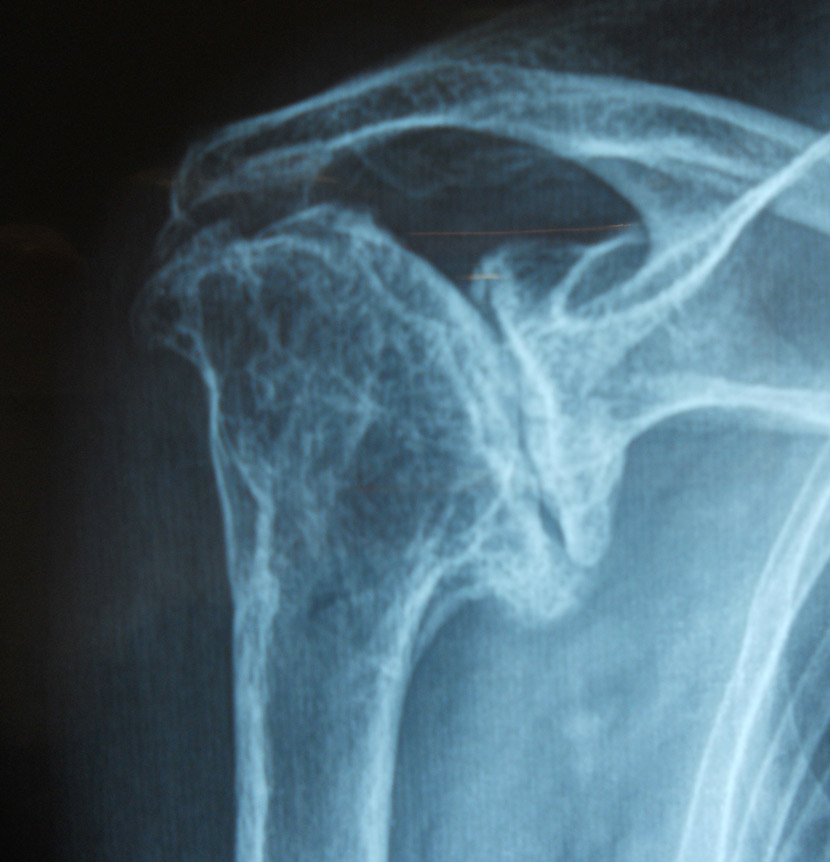

Fig.1 Radiografia preoperatoria con grave usura della glenoomerale e risalita completa della testa per rottura massiva e irreparabile della cuffia dei rotatori